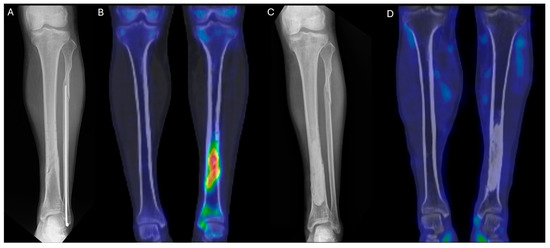

A 45-year-old man sustained an injury while riding a motorcycle and was diagnosed with closed mid-shaft fractures of the left tibia and fibula. At another hospital, he underwent open reduction and internal fixation. The tibia was fixed using a metal plate and screws, while the fibula was treated with intramedullary fixation.

Starting five months after the surgery, pus began to discharge from the wound. At 8, 12, and 14 months postoperatively, the patient underwent a total of three procedures at the same hospital, including removal of the tibial implant and debridement. Tissue cultures were performed during all three surgeries: one was negative, and two yielded methicillin-sensitive Staphylococcus aureus (MSSA).

As the infection did not improve, the patient visited our outpatient clinic. He had been receiving intravenous and oral ciprofloxacin for 10 months since the 8-month postoperative day. After the initial visit to our clinic, 99mTc DPD bone SPECT/CT scan was performed, revealing areas of increased uptake, as shown in the images below (Figure 5 and Figure 6).

The patient then underwent surgery, during which extensive debridement was performed on the suspected infected intramedullary lesion. Tissue culture was also taken from the site with the highest uptake on the SPECT/CT scan. Some intramedullary bone marrow was also removed. Antibiotic-impregnated bone cement was inserted into the debrided area.

After surgery, the patient received intravenous antibiotics for two weeks during hospitalization and continued with oral antibiotics for three weeks as an outpatient. At one month postoperatively, plain radiographs showed no specific findings, and at six months, a follow-up 99mTc DPD bone SPECT/CT scan confirmed the absence of high-uptake lesions, indicating that the infection had been successfully controlled. The patient remained free of recurrence and infection for two years.

Figure 5. (A) Preoperative lower leg AP X-ray. (B) Preoperative 99mTc DPD bone SPECT/CT coronal image. (C) Postoperative lower leg AP X-ray at 1 month. (D) Postoperative 99mTc DPD bone SPECT/CT coronal image at 6 months, showing no hypermetabolic uptake, consistent with infection control.